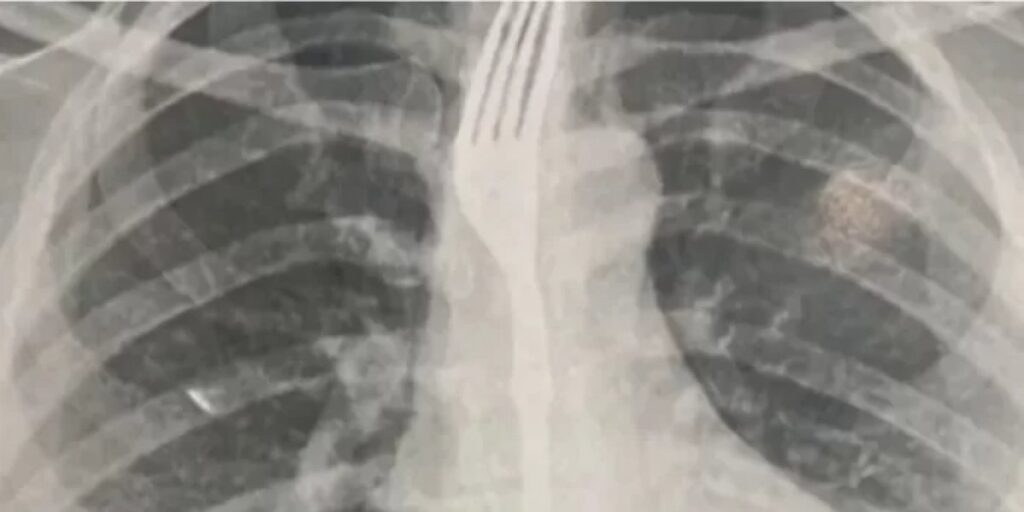

Um caso inusitado chamou a atenção da cidade de Guanambi. Uma mulher precisou de socorro após engolir um garfo enquanto fazia uma refeição. Ela foi levada ao Hospital Geral da cidade, onde exames de imagem identificaram o objeto alojado no esôfago em posição de risco.

Devido à gravidade, os médicos decidiram transferir a paciente para Vitória da Conquista, onde deve passar por um procedimento especializado para retirada do utensílio. O caso foi considerado de alta complexidade pela proximidade do garfo com órgãos vitais, o que impossibilitou a remoção imediata em Guanambi.